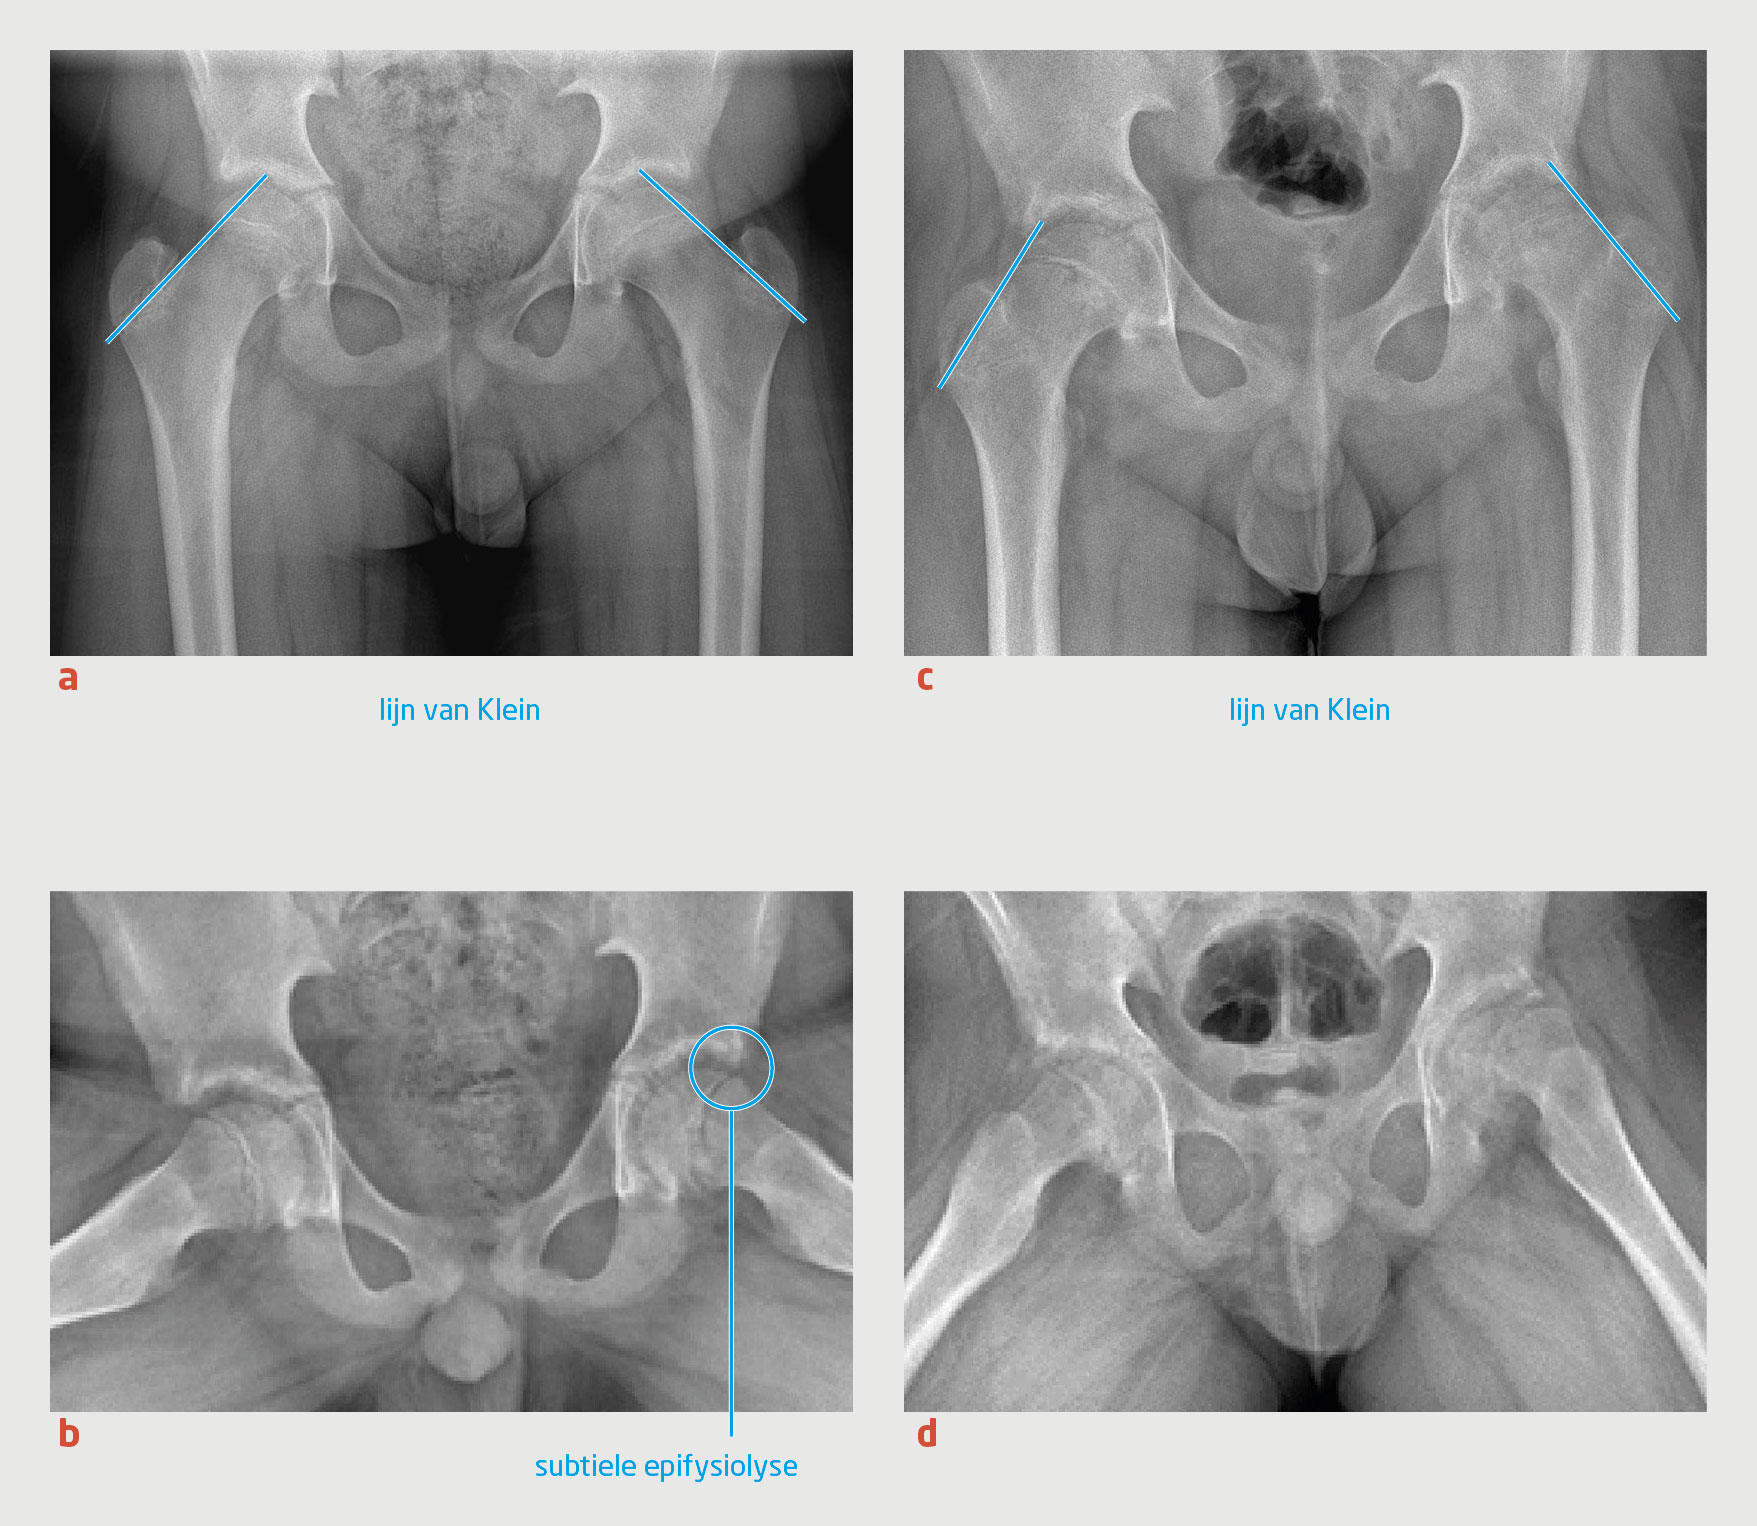

Wij schreven bedrust voor en opereerden patiënt de volgende dag, waarbij beiderzijds de epifyse van het caput ossis femoris werd gefixeerd middels percutane schroeven. Postoperatief moest patiënt 6 weken mobiliseren met krukken. Bij poliklinische controle na 1 jaar had patiënt een blokkadegevoel van de linker heup bij bukken en was er in beide heupen maximaal 10° endorotatie mogelijk. Het Drehmann-teken was beiderzijds aanwezig. Herhaalde röntgenopnames lieten de bekende standsafwijking van het caput ossis femoris zien, met een geringe sclerose van het acetabulum beiderzijds (figuur 5).

Figuur 5

Operatief gefixeerde epifyse van het caput ossis femoris

Figuur 5 | Operatief gefixeerde epifyse van het caput ossis femoris

Röntgenopnames van het bekken. (a) Anteroposterieure opname 1 jaar na schroeffixatie van het caput ossis femoris beiderzijds. (b) Gelijktijdige Lauenstein-opname.